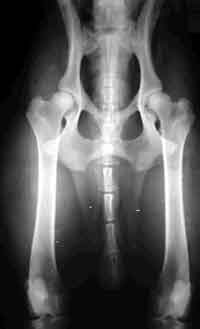

HD (Hüftgelenksdysplasie)

HD ist eine Fehlbildung der Hüftgelenke - das heißt Oberschenkelkopf und Gelenkpfanne passen nicht korrekt aufeinander. Diese Fehlbildung kann unterschiedlich ausgeprägt sein und tritt oft beidseitig auf.

Wir unterscheiden zwischen 5 verschiedenen Schweregraden der HD.

HD-frei - A

Das Gelenk ist absolut unauffällig und der Norbergwinkel beträgt 105 Grad oder mehr

HD-Verdacht/Grenzfall - B

Der Norbergwinkel beträgt 105 Grad oder mehr und die Gelenkpfanne und/oder der Schenkelkopf sind leicht ungleichmäßig oder aber Gelenkpfanne und/oder Schenkelkopf sind gleichmäßig, aber der Norbergwinkel beträgt weniger als 105 Grad

leichte HD -C

Norbergwinkel 100 Grad oder kleiner, ungleichmäßiger Oberschenkelkopf und Gelenkpfanne. Unter Umständen sind auch schon leichter arthrotischer Veränderungen zu bemerken.

mittlere HD - D

Norbergwinkel größer als 90 Grad und deutliche Ungleichmäßigkeiten von Oberschenkelkopf und Gelenkpfanne. Veränderungen des Pfannenrandes und/oder arthrotische Veränderungen sind zu erwarten oder schon vorhanden.

schwere HD - E

Norbergwinkel weniger ald 90 Grad, abgeflachter Pfannenrand, auffällige Veränderungen an Oberschenkelkopf und Gelenkpfanne. Deutliche arthrotische Veränderungen sind zu erwarten oder schon vorhanden.